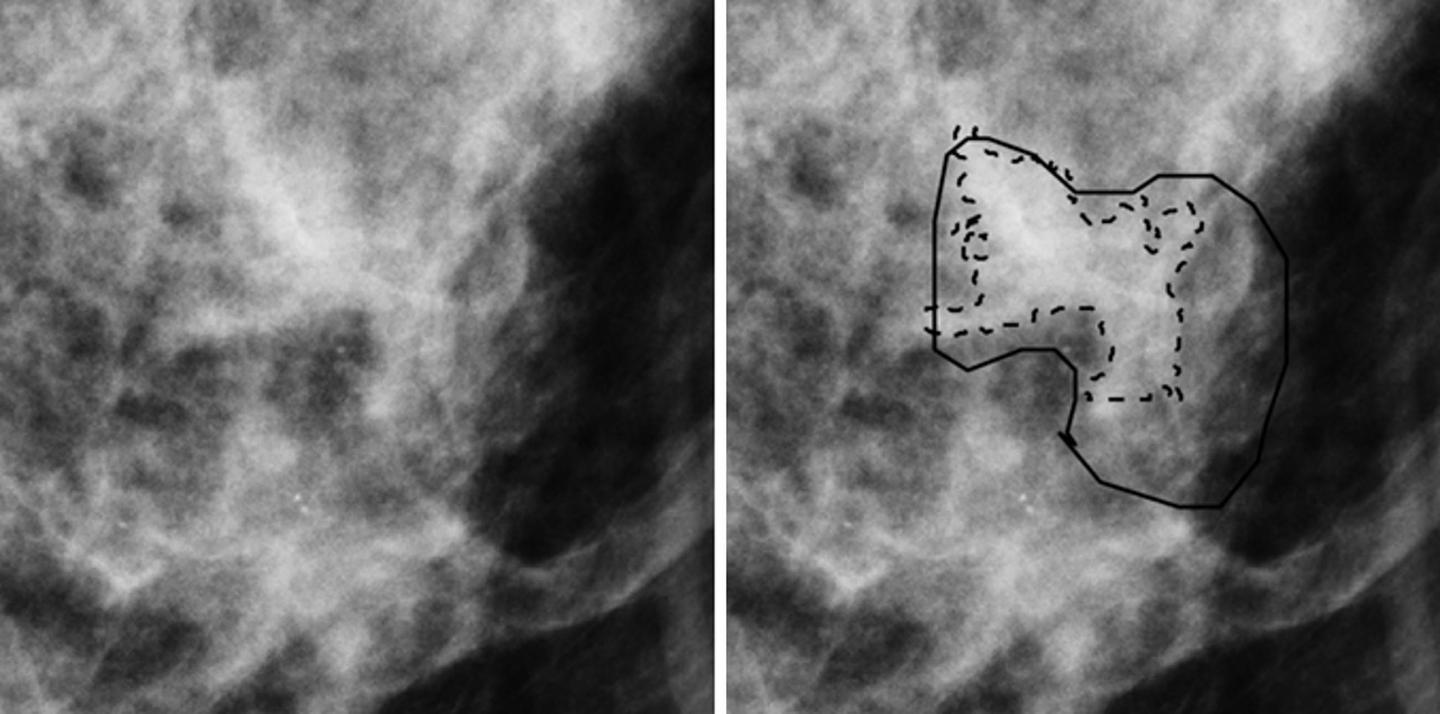

OAK BROOK, Ill. - A novel technique that uses mammography to determine the biological tissue composition of a tumor could help reduce unnecessary breast biopsies, according to a new study appearing in the journal Radiology .

Dr. Drukker and colleagues recently studied a new technique called three-compartment breast (3CB) imaging. John Shepherd, Ph.D., currently at the University of Hawaii in Honolulu, and his team developed 3CB while he was at the University of California in San Francisco. By measuring the water, lipid and protein tissue composition throughout the breast, 3CB might provide a biological signature for a tumor. For instance, more water in the tumor tissue might indicate angiogenesis, or the production of new blood vessels, an early sign of cancer development.

For the study, the researchers acquired dual-energy mammograms from 109 women with breast masses that were suspicious or highly suggestive of a malignancy--the types of lesions that typically would be biopsied--immediately prior to biopsy, and the ensuing biopsies showed 35 masses to be invasive cancers, while the remaining 74 were benign.

3CB images were derived from the dual-energy mammograms and analyzed along with mammography radiomics, a method that uses artificial intelligence algorithms to analyze features and patterns in images--some of which are difficult for human perception--developed by Maryellen L. Giger, Ph.D., and her team at the University of Chicago for use in computer-aided diagnosis on breast images.

The combination of 3CB image analysis and radiomics improved the positive predictive value, or the ability to predict cancer, in breast masses deemed suspicious by the breast radiologist. The combined method improved positive predictive value from 32 percent for visual interpretation alone to almost 50 percent, with an almost 36 percent reduction in biopsies. The 3CB-radiomics method missed one of the 35 cancers, for a 97 percent sensitivity rate.